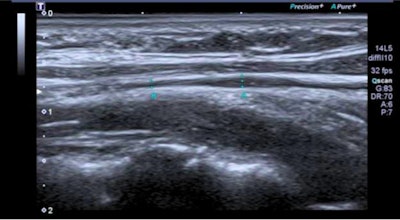

Six patients had mild vagus nerve thickening and higher echo on neck ultrasound scans. Thoracic ultrasound, meanwhile, showed flattened diaphragmatic curves in 10 patients. Ten out of 16 patients also showed reduced maximum inspiratory pressures.

"Radiologists may find by ultrasound in the lateral cervical area some images over the vagus nerve reflecting mild reactive inflammatory changes," Lladós said. "In addition, a flattened diaphragmatic curve visualized by chest ultrasound could translate into decreased diaphragmatic mobility during respiration."